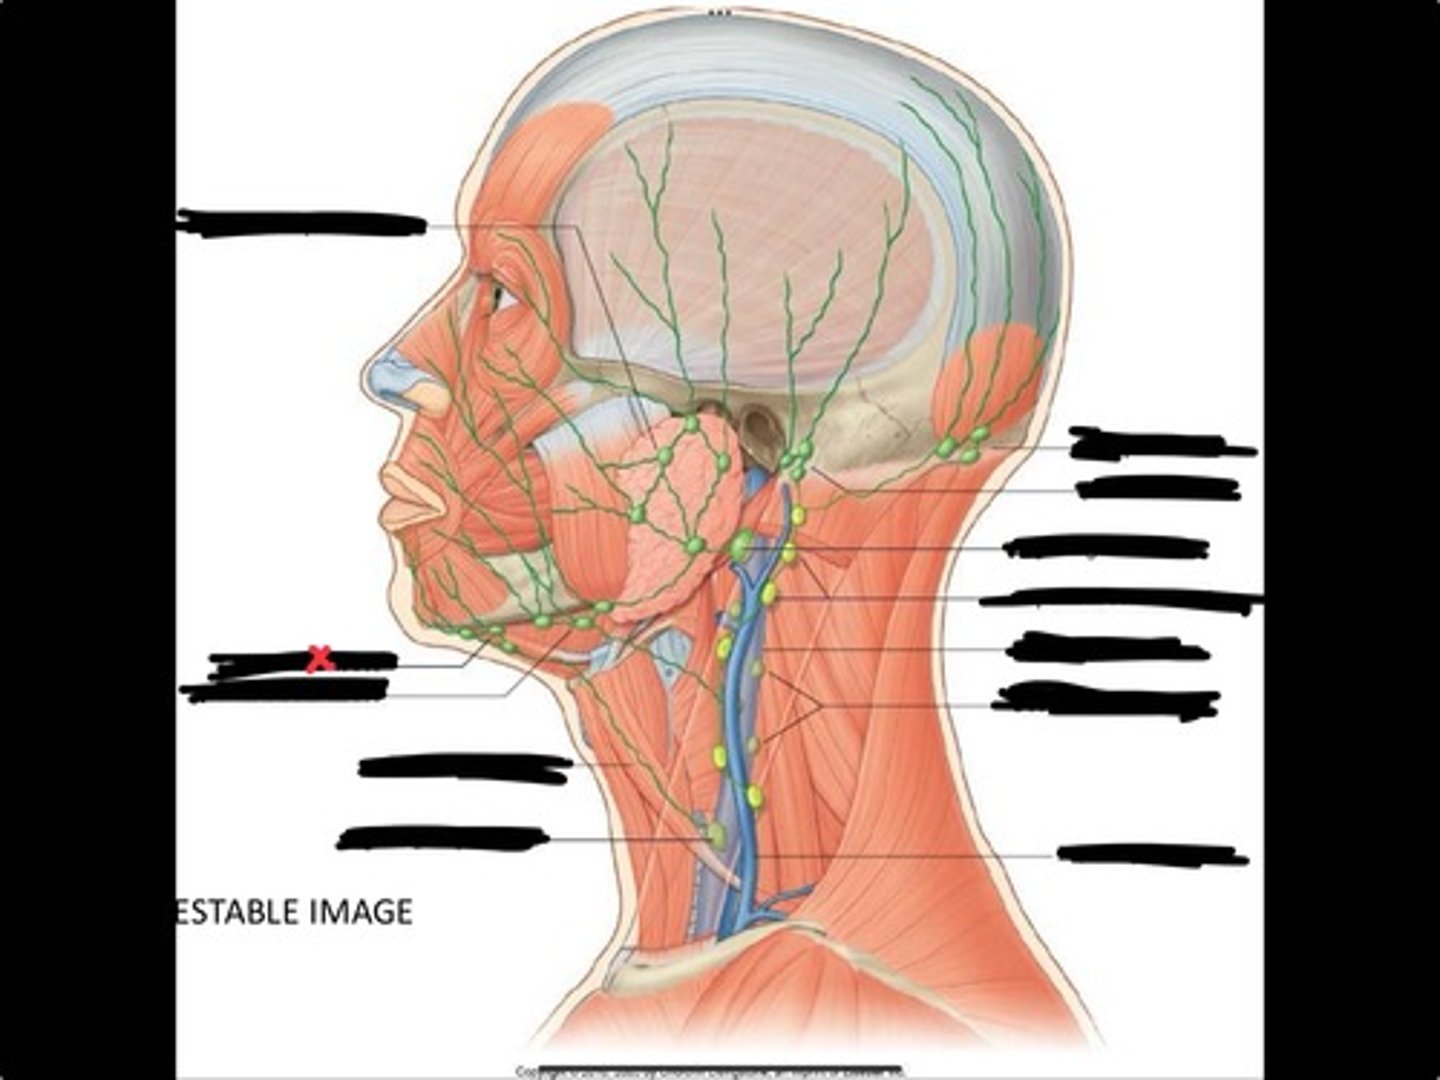

Jugulo-omohyoid node

Omohyoid muscle

Submandibular nodes

Submental nodes

Pre-articular/parotid nodes

Occipital nodes

Mastoid nodes

Jugulodigastric nodes

Superficial cervical nodes

Internal jugular vein

Deep cervical nodes

External jugular vein